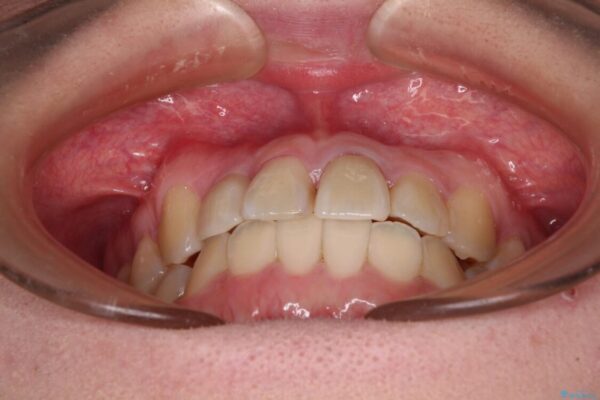

治療前

• 虫歯治療ついでに歯並びの後戻りを改善 インビザラインによる矯正治療 治療前画像

奥歯が痛いとのことで来院された患者様です。

治療計画

上顎親知らず周辺の炎症と、神経組織の失活した歯の炎症による痛みが認められたため、親知らずの抜歯と根管治療を行いました。

根管治療を行った歯はクラウンによる補綴治療が必要となりますが、高校生の頃に行った矯正治療の後戻りも気になるとのことで、補綴治療を行う前に矯正治療を行うこととしました。

後戻りは軽度であり、インビザラインにて歯列を整え、その後にオールセラミッククラウンにて補綴治療を行うこととしました。